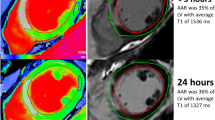

Differences of AAR, infarct size and microvascular damage and LV functional parameters according to the time between revascularization and CMR

Results are summarized in the Table 2. AAR remained stable across TRevasc-CMR tertiles (Fig. 2). Overall 46 (28%) patients showed IMH on T2-mapping. Occurrence and extent of IMH did not differ among TRevasc-CMR tertiles. IS and occurrence and extent of MVO as well as myocardial salvage index were comparable throughout TRevasc-CMR tertiles (Fig. 2). LV end-diastolic volume index increased slightly across TRevasc-CMR tertiles, so that patients in Tertile-3 patients had larger volume than those in Tertile-1. LV end-systolic volume index, regional and global systolic function parameters were comparable across TRevasc-CMR tertiles.

T2 relaxation times in infarct and remote regions

T1 relaxation time and extracellular volume fraction in the infarct and remote regions

T1 values of infarct and remote regions were measured in the target-slice of 124 patients. Overall, T1 of infarct was higher than that of remote region throughout TRevasc-CMR tertiles, and as compared to normal values of our centre (997 ± 27 ms, range: 943–1051 ms), (Fig. 1-Supplemental Material). Infarct T1, paralleling the behavior of T2, increased with the increase of TRevasc-CMR tertiles,. Post-hoc analysis revealed that T1 values increased from Tertile-1 to Tertile-2 without further increase from Tertile-2 to Tertile-3. By dichotomizing patients based on the presence or absence of IMH, only those without IMH increased infarct T1 value with the increase of TRevasc-CMR tertiles, mirroring the results of T2 (Fig. 2-Supplemental Material). When patients were divided according to pre-PPCI residual blood flow, both subgroups showed significant increase of T1 value in the infarct region with the increase of TRevasc-CMR tertiles (Fig. 3-Supplemental Material). We calculated ECV of the infarct and remote regions in patients without MVO (n = 68), given that state steady of gadolinium-based contrast agent cannot be reached between MVO (LGE-negative) and infarct (LGE-positive). Infarct and remote ECV values were comparable throughout TRevasc-CMR tertiles (Fig. 4-Supplemental Material).

Recent reports generated intense discussion on the dynamic changes of CMR-derived measures of ischemic damage in early post-STEMI phase with particular emphasis on myocardial edema. In elegant experimental studies [6, 7, 9], Fernàndez-Jiménez et al. showed that edema features a bimodal pattern after reperfusion. An initial wave of edema appears abruptly and very early (≤3 h) to be attenuated at 24 h and followed by a second edema wave peaking at 4 to 7 days. The same group described this bimodal pattern in a selected cohort of 16 reperfused STEMI patients undergoing serial CMR (8). In patients, the authors found that T2 values within the ischemic region, as measured by T2-mapping, varied consistently throughout the post-reperfusion phase paralleling the experimental results. Accordingly, AAR, as quantified by T2-weighted short-TI (T2w-STIR), changed substantially with the timing of CMR being significantly lower at 24 h than at hyper-acute (≤3 h) or at 4 and 7 days after reperfusion. In line with these findings, we observed that T2 of the infarct increased with the increase of timing of CMR after revascularization, with a steep augmentation between Tertile-1 (median: 1.0 day) and Tertile-2 (median: 2.7 days) without further change between Tertile-2 and Tertile-3 (median: 5.3 days). However differently from the above study, we found that T2-map-derived AAR did not vary with the timing of CMR after PPCI. This discrepancy can be ascribed to the differences in study populations and, most importantly, to the different techniques utilized for AAR quantification. While Fernàndez-Jiménez’s et al. utilized T2w-STIR, we used T2-mapping, which allows more robust, precise and reproducible estimation of infarct-related edema as compared to T2w-STIR [14, 15]. Different from T2w-STIR imaging, T2-mapping consents to measure T2 lengthening of the ischemic tissue due to increased water content, rendering this techniques particular sensitive to subtle changes in T2 relaxation times [14, 17, 19]. Differently, T2-weightening relies on relative signal intensity differences between ischemic and remote myocardium, which are influenced by several factors in addition to edema per se, such as specific T2-weightening parameters, motion-related signal loss in the lateral wall or selection of window/leveling to display images [15]. Accordingly, slight differences in T2 relaxation times between ischemic and remote myocardium, such as those reported in the experimental and clinical studies by Fernàndez-Jiménez et al. [6,7,8,9] at 24-h after reperfusion, might have been overlooked by T2w-STIR leading to underestimation of AAR. In our study, T2 values of infarct myocardium exceeded largely those of remote region irrespective of the time interval between revascularization and CMR, the presence or absence of IMH, and pre-PPCI residual blood flow in the myocardium at risk. Accordingly, we were able to quantify AAR on T2-maps using a semi-automatic threshold-based algorithm in the overall population and specific subgroups [17]. Moreover, the pattern of T1 values in infarct and remote myocardium paralleled closely that of T2, corroborating our study results. Experimentally T1 relaxation time increases in parallel with increasing myocardial water content, and prolonged T1 has been reported in myocardium at risk in STEMI patients [20, 21].